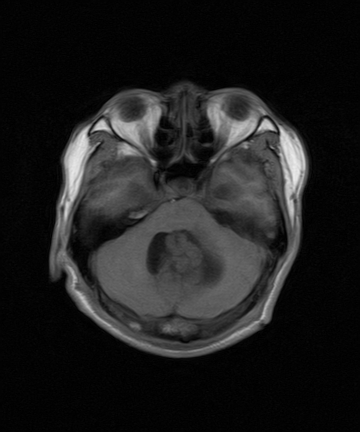

标题: MRI2064:少见病例。男性52,视力下降多年。 [打印本页]

标题: MRI2064:少见病例。男性52,视力下降多年。

四脑室区见混杂信号占位影,脑室系统扩张明显,临近结构显著受压称位,患者52岁,多考虑室管膜瘤可能性大

考虑第四脑室室管膜瘤并梗阻性脑积水;部分性空蝶鞍;左侧上颌窦粘膜下囊肿。

1、四脑室肿瘤并并脑积水。考虑室管膜瘤可能性大,脑膜瘤等排。

2、左侧上颌窦及蝶窦囊肿。